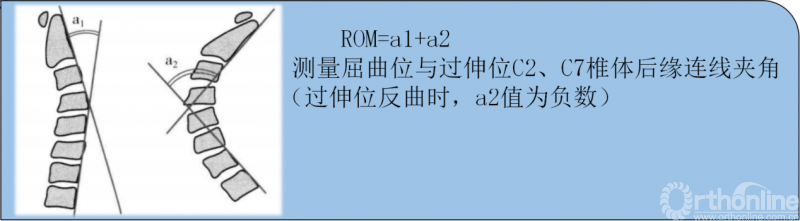

①术后颈椎总活动度(ROM)减少;

①轴性症状与颈椎总活动度(ROM)的关系

AS与术后颈椎总活动度(ROM)的减少密切相关,有助于减少ROM下降的措施可能有利于减少术后出现的轴性症状。

● Wada对41例接受了单开门手术的患者随访11年,16例(40%)有AS,ROM下降40%;

● Satomi报道51例单开门术后1年有3例(6%)严重颈背痛,ROM下降45%;

● Kawaguchi发现术后有AS的患者的ROM值下降明显高于无AS的患者。